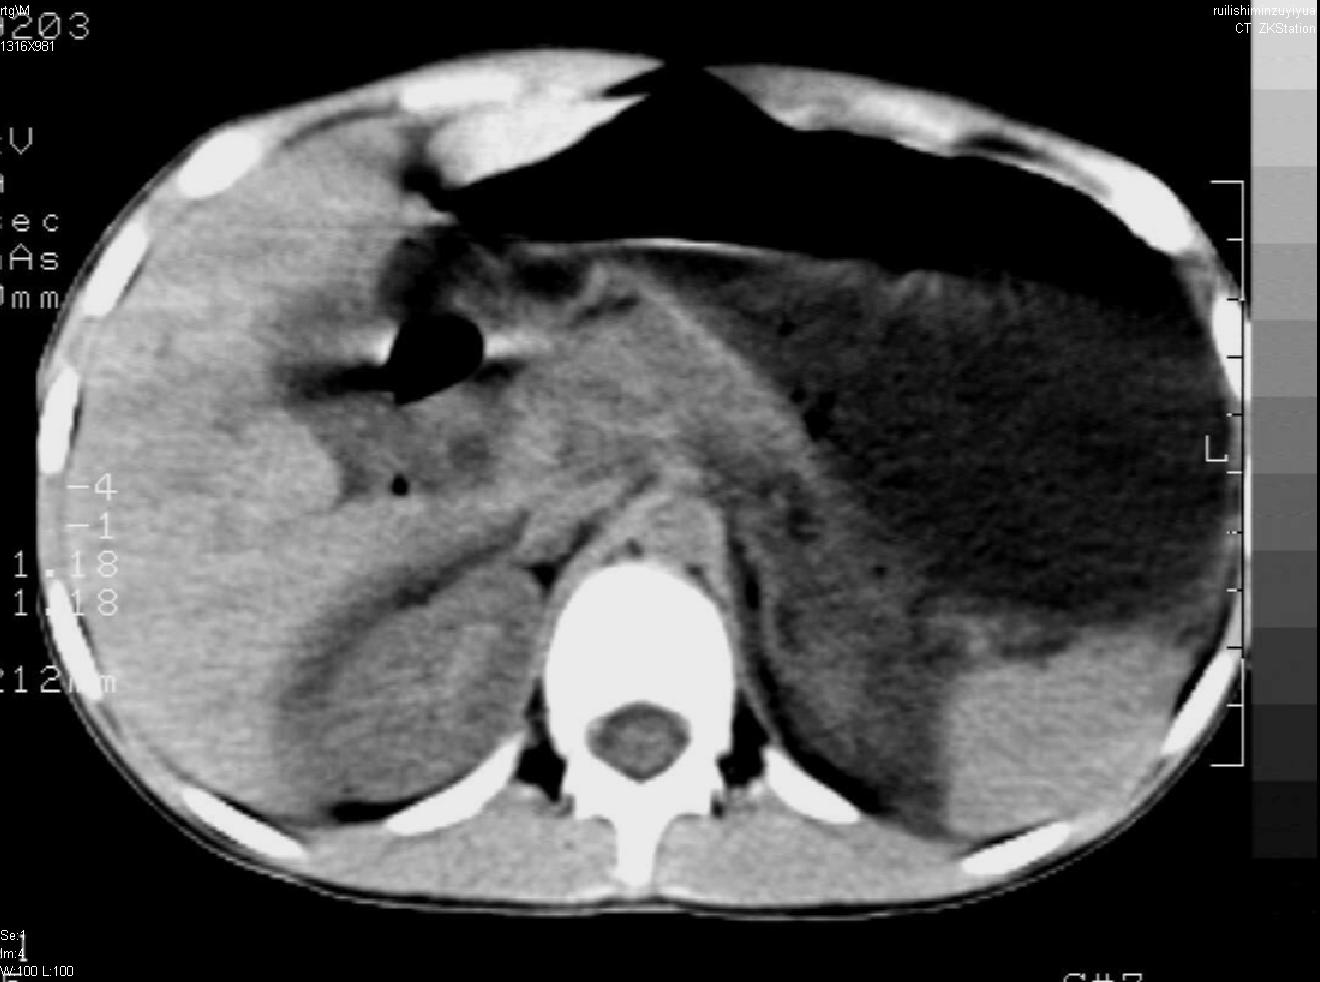

标题: PED0282:女,10岁,上腹疼痛2周 [打印本页]

标题: PED0282:女,10岁,上腹疼痛2周

b超:胆囊结石。疑坏死性胰腺炎

支持小儿急性坏死性胰腺炎。

1.水肿型胰腺炎  约占80%~90%,胰腺全部或局部水肿、充血,体积增大,胰液的排出受阻,因而使血液及尿中淀粉酶增高。

2.出血坏死型胰腺炎  约占10%~20%,病变急剧,因缺血、出血或坏死,胰腺呈深红色或紫黑色,大量渗出液包含胰液流入腹腔而引起弥漫性腹膜炎,可发生休克,甚至死亡。此时富有消化力的胰液渗出,作用于脂肪丰富的大网膜、肠系膜等,造成广泛脂肪坏死灶,将脂肪分解为甘油和脂肪酸。后者又吸取血中钙质形成钙化灶。血钙可显著降低而出现手足搐搦现象。